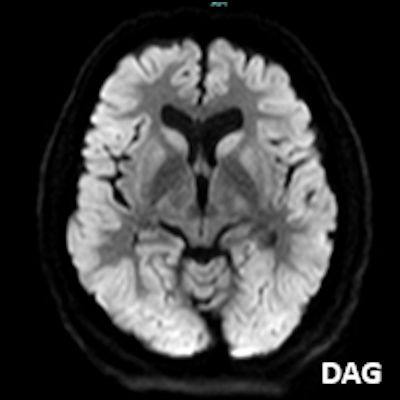

- A) Bilateral serebral kortekste (oklar) ve bazal ganglionlarda (oklar) yaygın DAG hiperintens, ADC hipointens difüzyon kısıtlamaları görülüyor.

- B) 9 gün sonraki difüzyon MR incelemede kortikal ve bazal ganglionlardaki difüzyon kısıtlamalarının gerilediği, bilateral serebral beyaz cevherde (oklar) ve internal kapsül arka bacağı- kortikospinal trakt boyunca (oklar) yaygın DAG hiperintens, ADC hipointens difüzyon kısıtlamalarının geliştiği izleniyor.